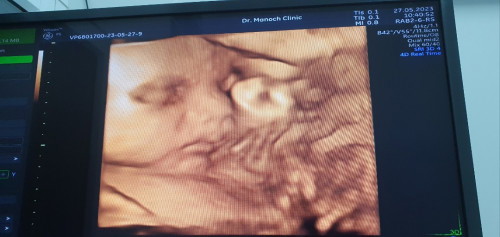

ทีมสิงหาคม 27วีค

27วีค น้องหนัก 1145กรัม แม่ๆบ้านอื่นน้ำหนักน้องถึงใหนกันบ้างคะ

อยากเห็นหน้าลูกแบบนี้บ้างจังแต่ลูกไม่ให้ความร่วมมือเลย😂😂